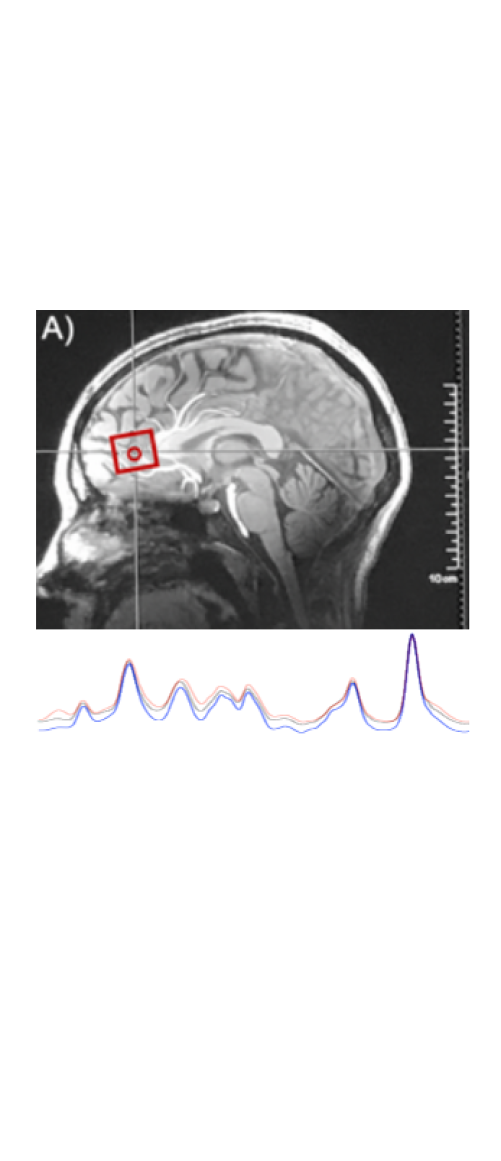

A 7T fMRI and C MRS dataset with resting state and task based data, imaged on various age cohorts, to identify the affect of aging on network connectivity.